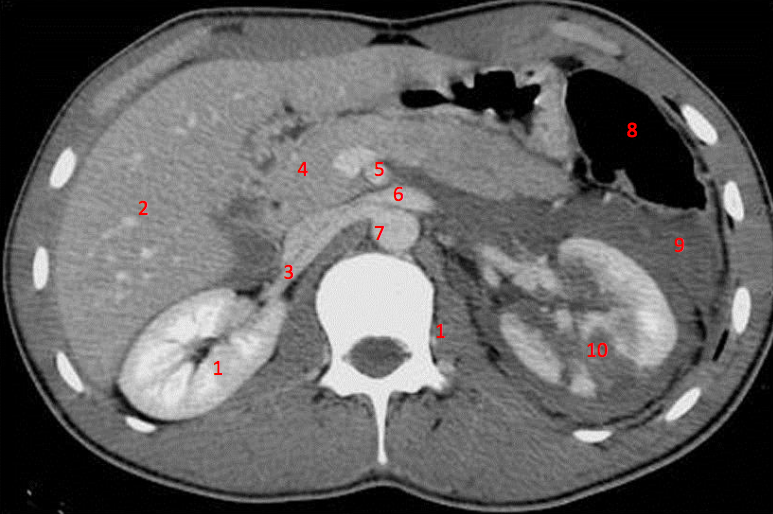

Number 3?

IVC

Number 1?

R Kidney

Number 2?

Gall bladder

Number 8?

Body of thoracic vertebra

Number 9?

Lt rib

Number 7?

Unlabeled

Number 4?

Rectus abdominus

Descending colon

Rt lobe of liver

Number 10?

Rt rib

Head of pancreas

Number 6?

Stomach

Number 5?

Rt ureter

Superior mesenteric artery